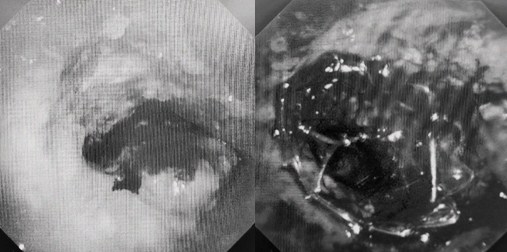

患者入院第二天,在麻醉手術(shù)中心全力配合下,歐陽海峰帶領(lǐng)呼吸介入團(tuán)隊(duì),歷時(shí)40分鐘快速置入硬質(zhì)支氣管鏡、鏟切腫瘤,并順利植入全覆膜TTS支氣管金屬支架?;颊邭舛贪Y狀即刻緩解,為患者贏得了寶貴的后續(xù)治療機(jī)會。